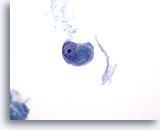

画像 4

肺FNA、肺腺癌

波状縁を呈する悪性腺細胞の集塊。背景には何も見られず、腫瘍性背景を呈していません。悪性細胞の保存状態は良好です。細胞質には、離散性の空胞が微細なものから大きなものまで見られ、一部には取り込まれている好中球が認められます。 60倍

画像 4

肺FNA、肺腺癌

波状縁を呈する悪性腺細胞の集塊。背景には何も見られず、腫瘍性背景を呈していません。悪性細胞の保存状態は良好です。細胞質には、離散性の空胞が微細なものから大きなものまで見られ、一部には取り込まれている好中球が認められます。

60倍